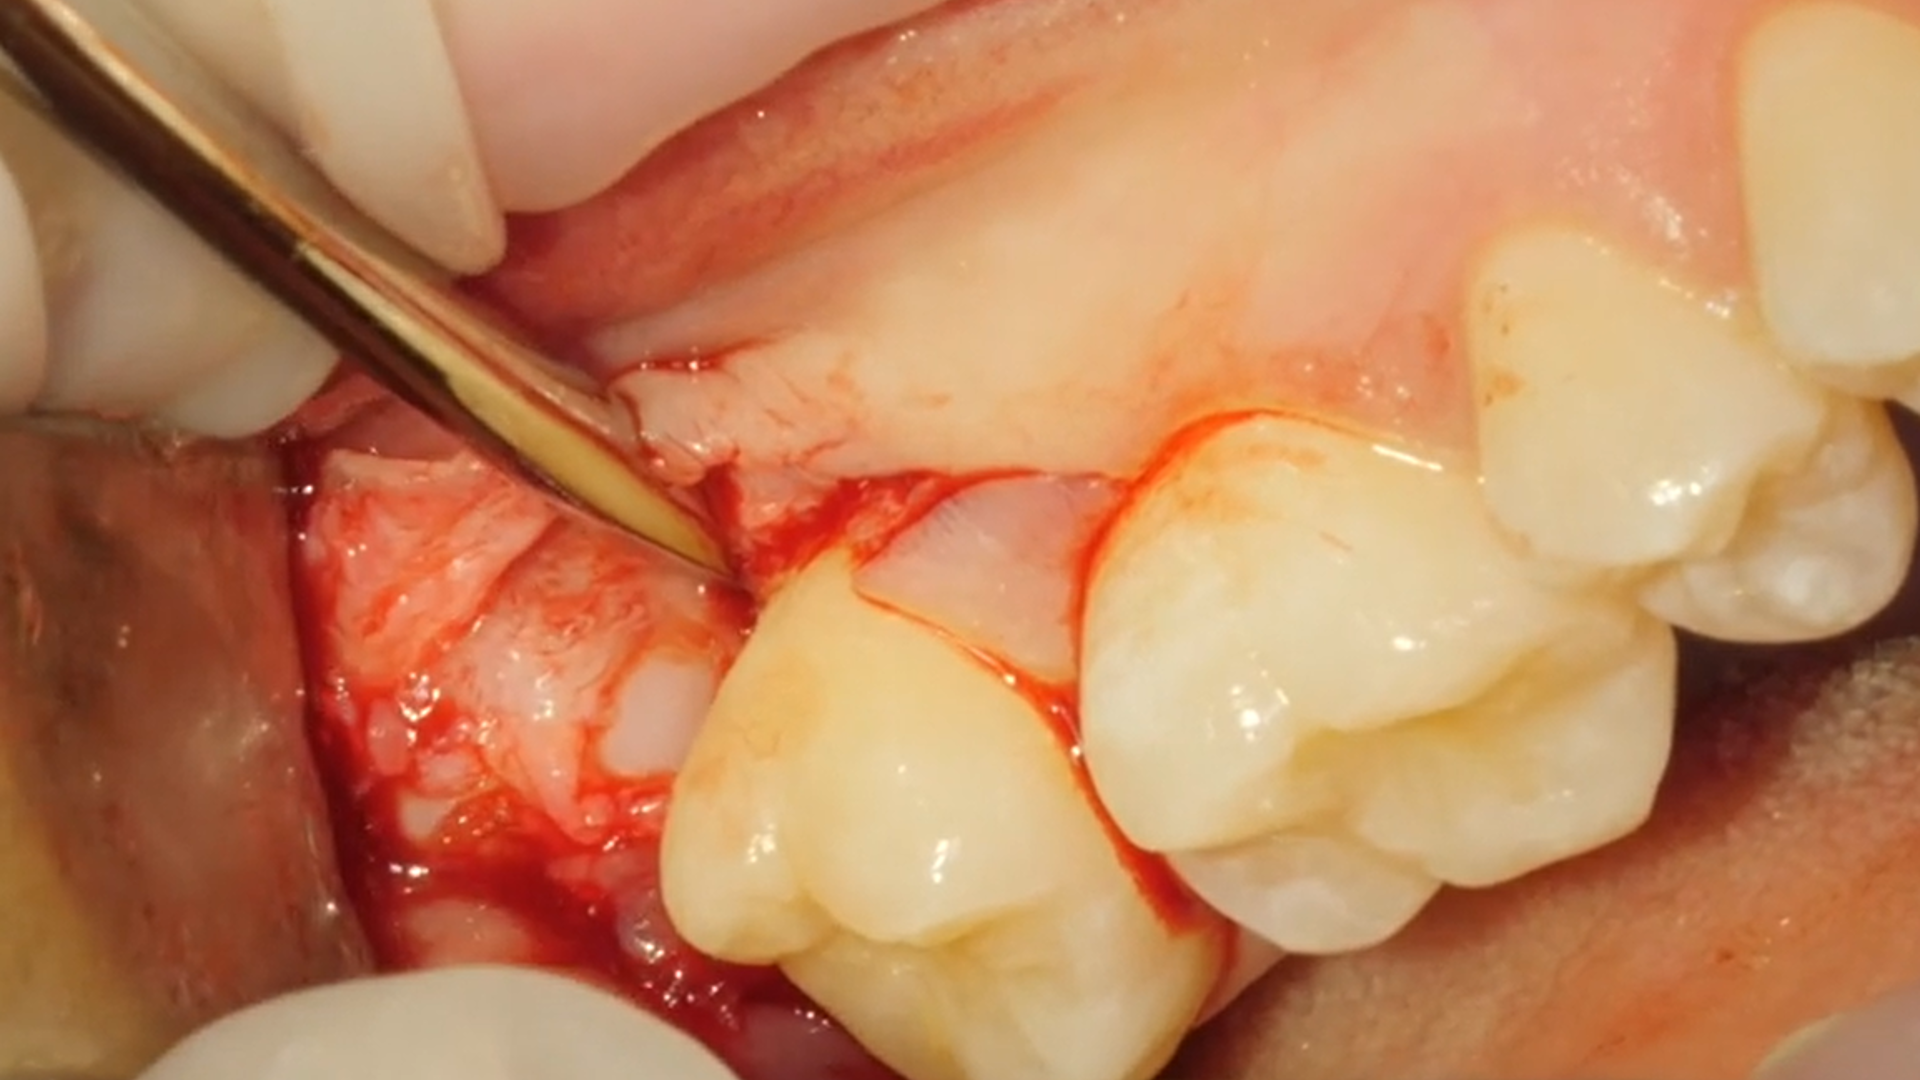

Lower right impacted third molar removal [4 8]